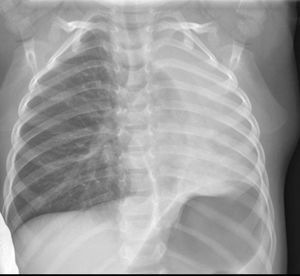

Se ingresa con el tratamiento de antibioterapia empírica (ampicilina y azitromicina) y terapia nebulizada con beta-2 adrenérgicos y budesonida. A las 48h, ante la ausencia de mejoría clínico-radiológica se realizó broncoscopia flexible que puso de manifiesto la existencia de material mucoso blanquecino a la entrada de bronquio principal izquierdo, que se aspiró parcialmente. Se completa procedimiento con broncoscopia rígida, y se visualiza molde bronquial a nivel de língula y bronquio superior izquierdos que se extrae con pinzas y aspiración (fig. 2).